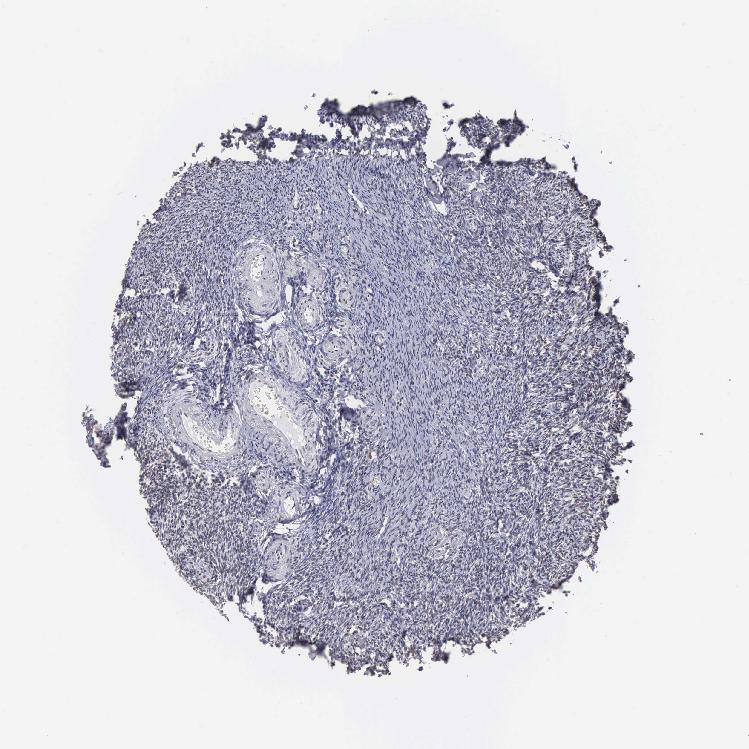

OVARY - Antibody stainingi

Antibody staining in the annotated cell types in the current human tissue is reported as not detected, low, medium, or high, based on conventional immunohistochemistry profiling in selected tissues. This score is based on the combination of the staining intensity and fraction of stained cells.

Each image is clickable and will lead to virtual microscopy that enables deeper exploration of all samples and also displays staining intensity scores, fraction scores and subcellular localization as well as patient and tissue information for each sample.

Antibody HPA000427Antibody CAB004680

Follicle cells Medium-

Ovarian stroma cells Not detectedMedium